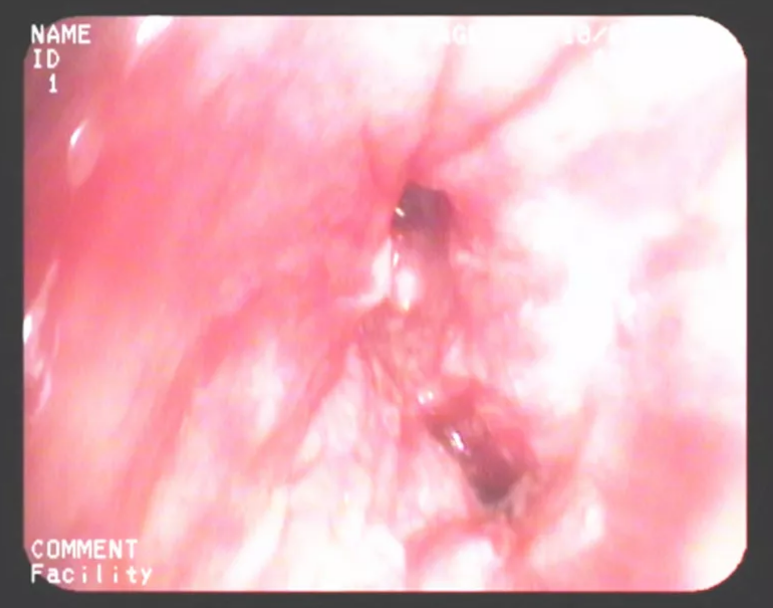

2+月前患者再次出現(xiàn)咳嗽伴活動(dòng)后呼吸困難、咯血,就診于川北醫(yī)學(xué)院呼吸與危重癥醫(yī)學(xué)科。經(jīng)過(guò)電子支氣管鏡檢查發(fā)現(xiàn)患者右肺下葉基底段支氣管殘端表面充血腫脹,呈結(jié)節(jié)狀改變,觸之易出血,可見(jiàn)少許壞死物覆蓋。病理活檢提示鱗癌,考慮支氣管殘端肺癌復(fù)發(fā)。

治療前